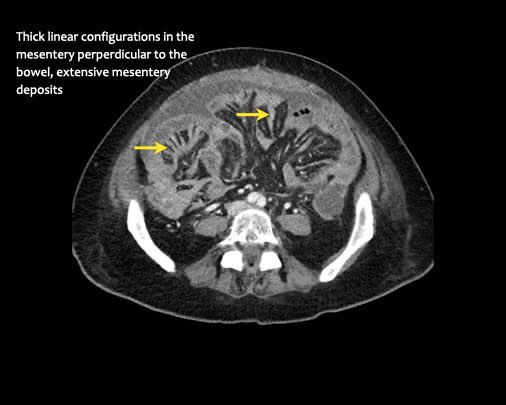

Cần tìm kiếm các tổn thương dạng nốt hoặc đường thẳng dày được bao quanh bởi mỡ ở phía mạc treo của ruột.

Hình ảnh

Hình ảnh CT của một bệnh nhân ung thư phúc mạc.

Một lượng nhỏ dịch cổ trướng hiện diện ở góc phần tư trước bên phải.

Các đường dày dạng nốt vuông góc với thành ruột được ghi nhận.

Hình ảnh này đại diện cho tổn thương xâm lấn mạc treo ruột lan rộng (mũi tên).